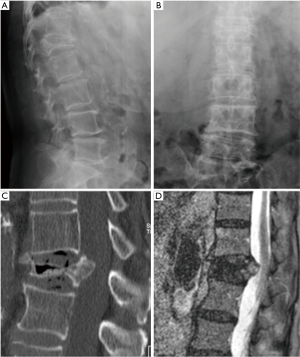

All the nine patients were in theory suitable for corpectomy and expandable titanium cage implant (7). But this approach was performed only in two of them. In fact, in 7 patients, a reconstruction of the anterior and medial spinal column was accomplished by third generation percutaneous vertebral augmentation systems (MK). In all the cases however a posterior fixation with rod and screws was always performed. The choice between one technique and the other one was made according to the signal in short tau inversion recovery (STIR) in the MRI sequences: in case of hyperintense signal to the level of the collapsed vertebra (VP), we decided for the percutaneous vertebral augmentation (Figures 3,4) (8). In absence or in case of very low STIR hyperintense signal, we chose for the standard corpectomy (Figures 5,6). Indeed, the presence of positive signal in the VP is in fact indicative of the reducibility of the vertebral soma. Moreover, in the cases of spinal canal compression the applicability of the third generation MK alone, without any posterior decompression, must not be excluded: it must be inferior to 1/3 and 2/3 respectively in case of fractures level above and below the spinal cord and any clinical signs of radicular compressions must not be identified. Otherwise, a direct posterior spinal cord decompression must be performed. Furthermore it is mandatory to evaluate the state of the anterior longitudinal ligament (ALL). In case of ossification of ALL at the level of the VP, MK has to be avoided, because a satisfactory correction of the vertebral height and a substantial management of the regional deformity might not be achieved. Mean follow-up was 18 months (range, 12–28 months). None of the patients experienced neurologic deterioration neither they showed a progression of local or regional deformity. No infections, dural tears, or spinal cord injuries occurred. No revision surgery was performed. In case of corpectomy the main blood loss and the mean surgical time were inevitably greater (9).